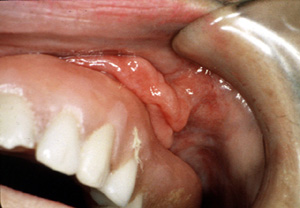

| Esta vista más

aumentada de la lesión del lado izquierdo

está compuesta de por lo menos tres pliegues de tejido bastante

denso. Hay invaginaciones profundas entre los pliegues.